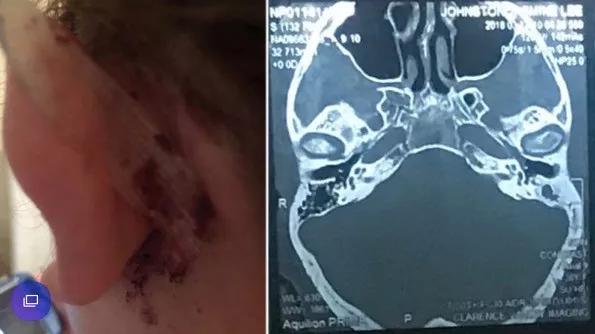

38岁的澳洲妈妈Jasmine Small和其他很多人一样,她也有用棉签棒掏耳朵的习惯。

2016年底,她发现左耳听觉出了问题,有时根本听不到任何声音!

这种情况大概持续了7、8个月后,情况开始慢慢恶化。

当她再用棉签掏耳朵时,左耳总是感觉很疼,有时候还会有棕色的、难闻的液体流出,甚至还有血丝。

意识到情况不妙,Small赶紧上医院检查。

一开始,医生也认为情况不严重,只是轻微感染,给她开了些抗生素让她回家服用。

然而并没有什么效果。

2017年底,Small换了位耳鼻喉科专家后,才发现情况已经非常严重。

医生非常严肃地告诉她,必须立即手术,不然会有生命危险。

Small吓了一跳,只能推迟和丈夫的蜜月旅行。

CT扫描显示,Small的耳朵深处已被感染,这里非常靠近她的大脑。

而这一切竟然都是由于棉签上松散棉线引起。

更令人难以置信的是,医生断定,耳朵里的这些小棉块已堆积了长达五年之久!

很快,Small经历了一场大手术,最终保住了性命,但她的左耳已遭到永久性损害,接下来她还需要面临一系列恢复手术,甚至佩戴助听器。